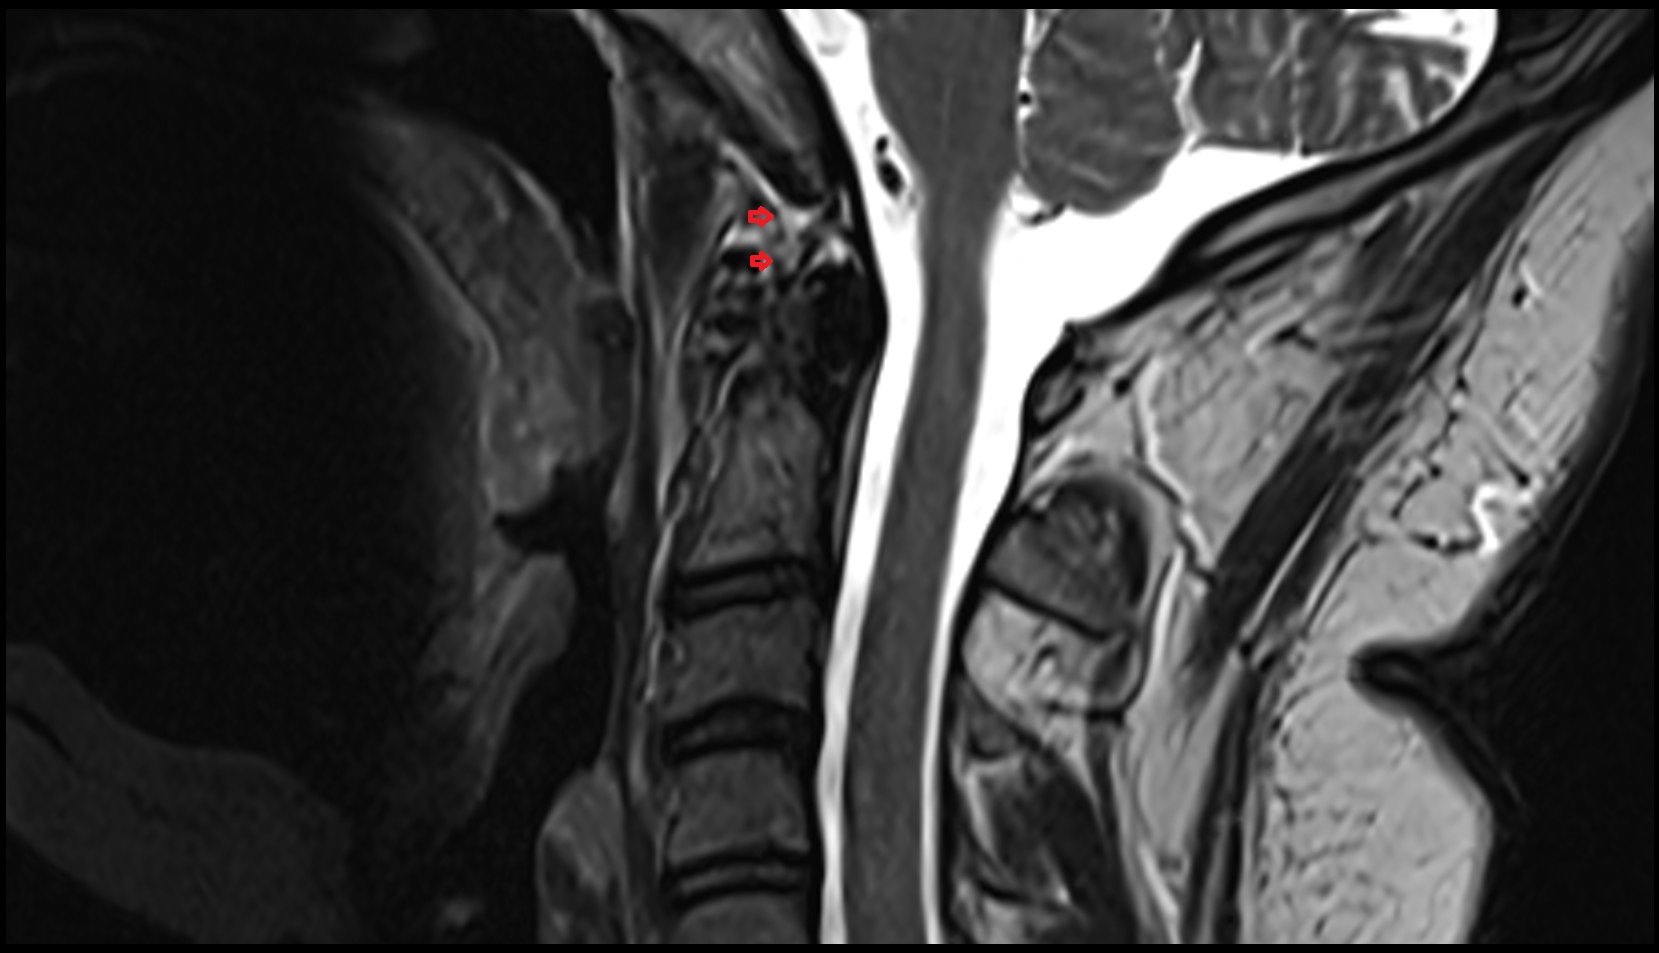

- Spinal cord

- Upper cervical spinal cord